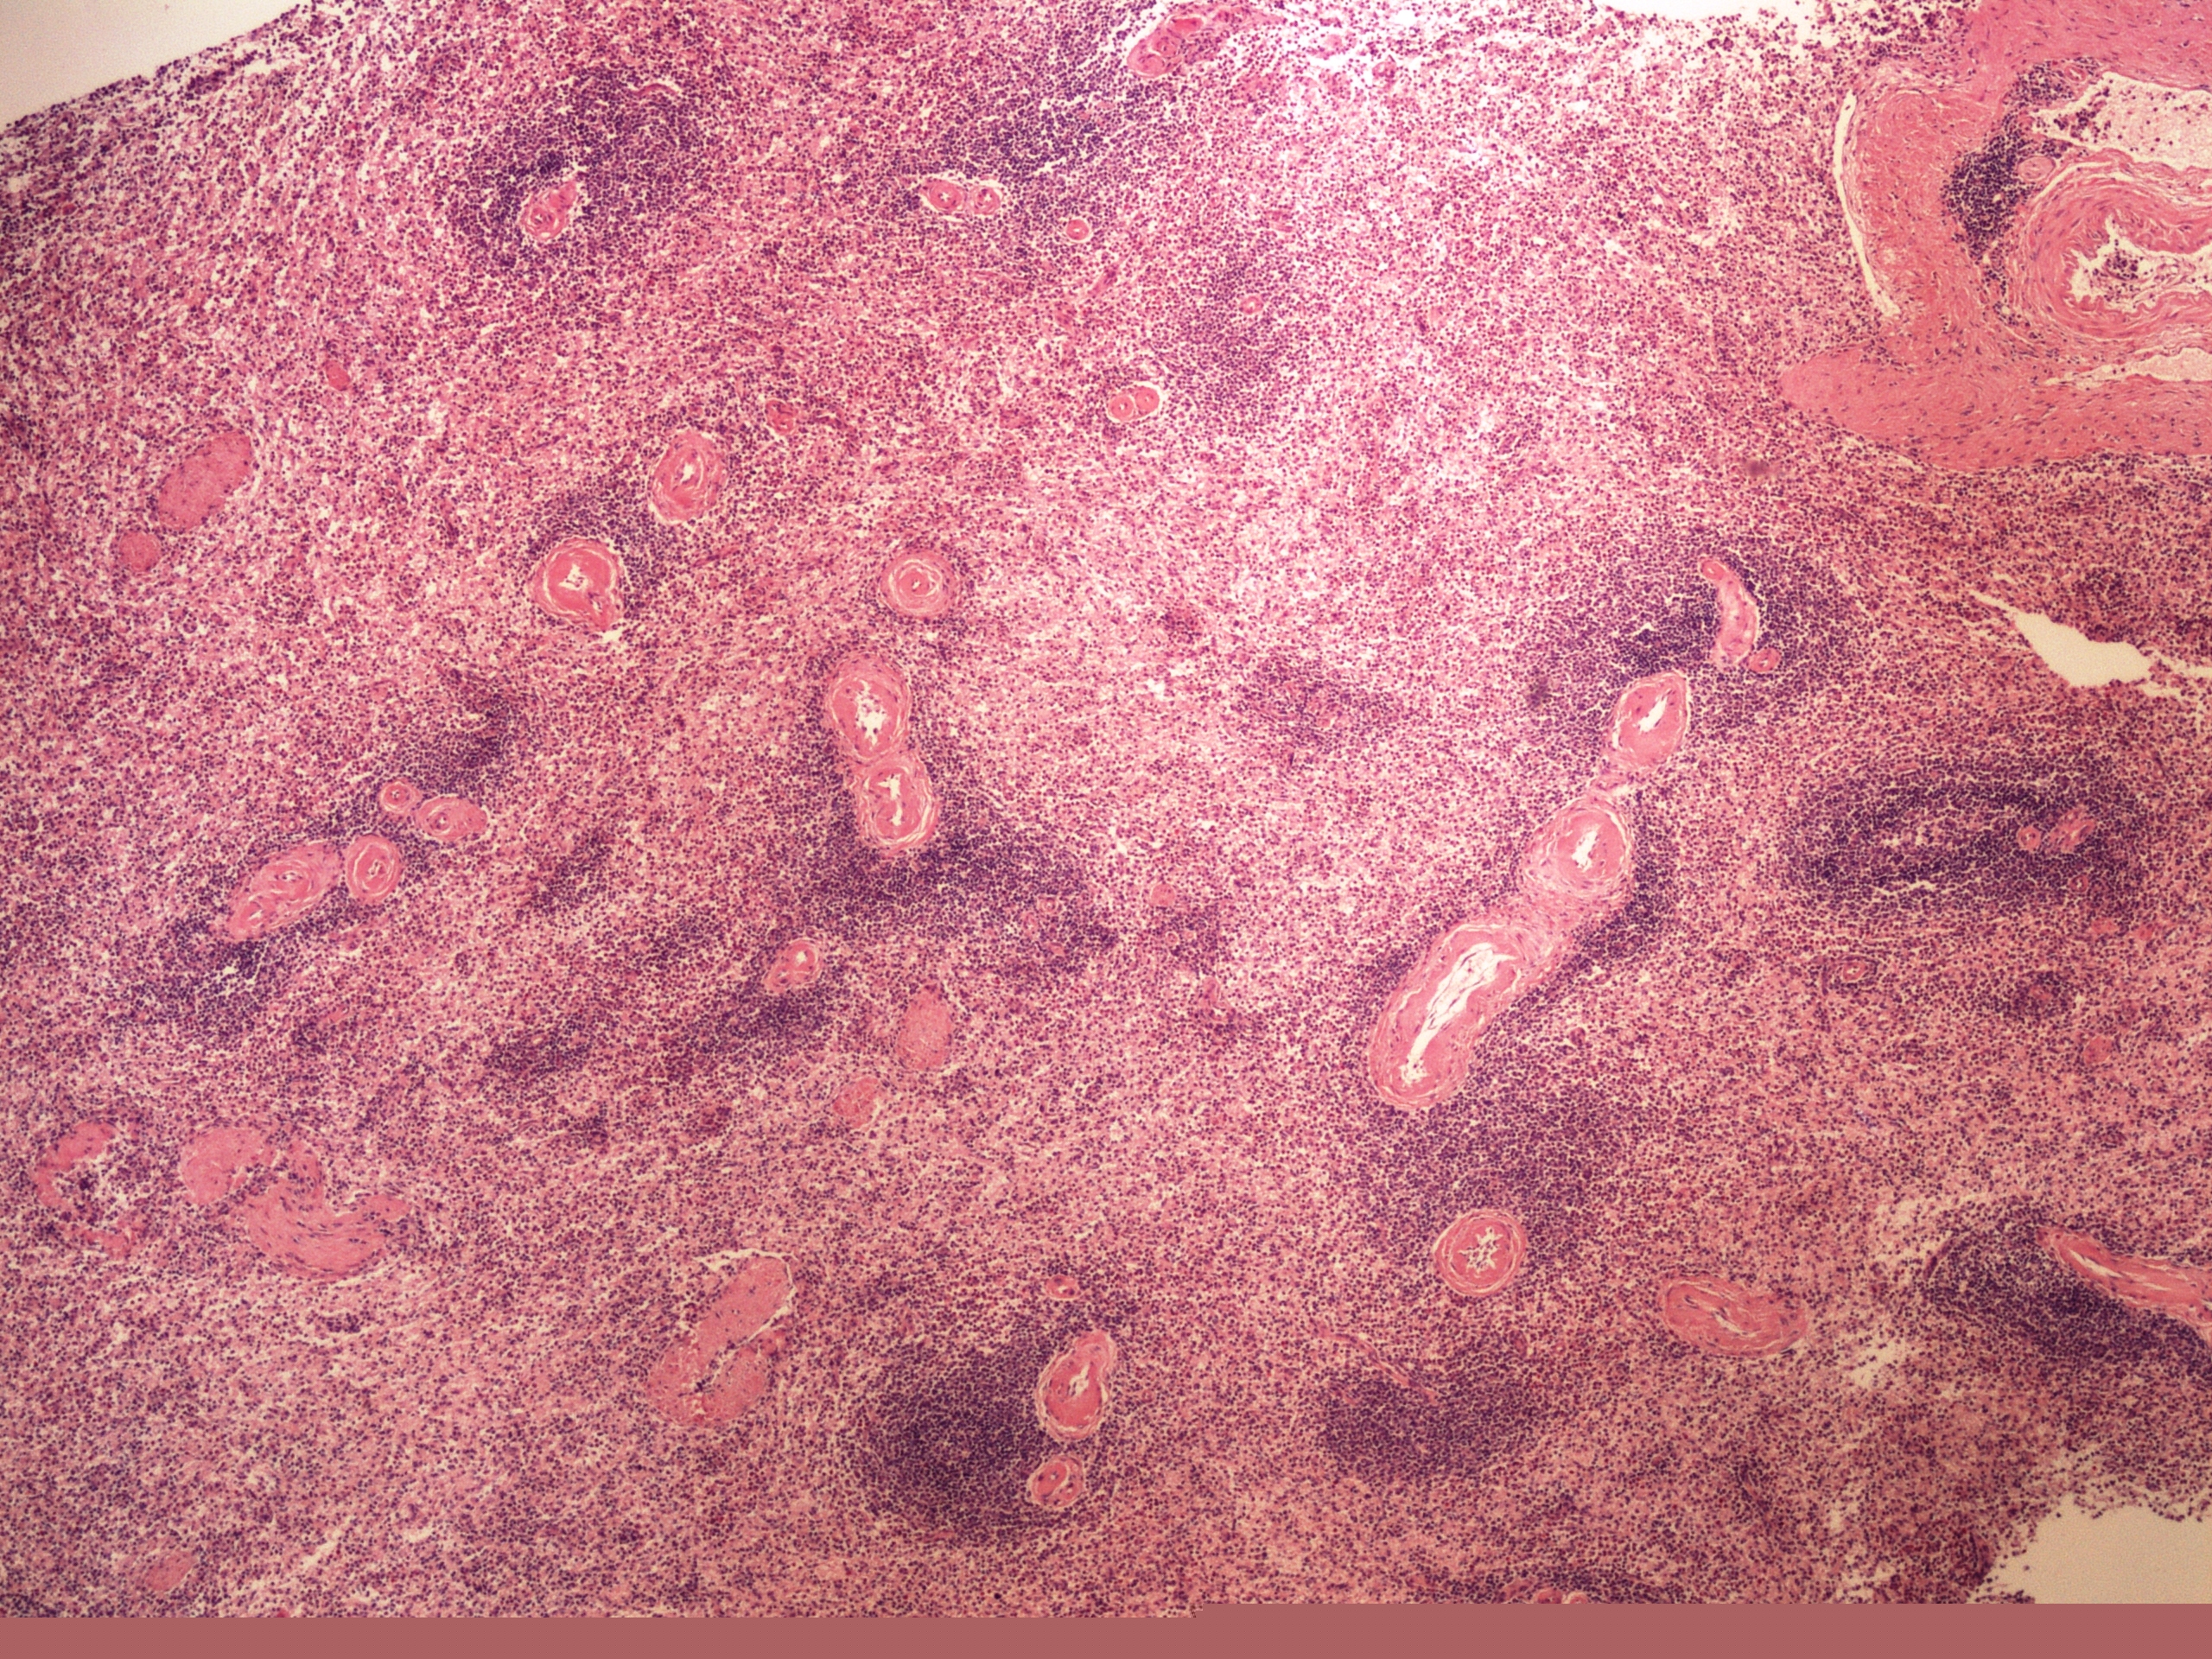

Preparát č.17 a č.18 - perisplenitis cartilaginea

Struktury

- ložiska vaziva